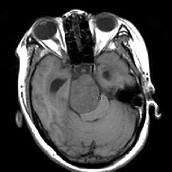

问题 女,32岁,头痛、右侧肢体功能障碍约1年,声间嘶哑,饮水呛咳,请根据所提供图像,选择最可能的诊断()

选项 A.(斜坡)脑膜瘤 B.(斜坡)脊索瘤 C.(斜坡)神经鞘瘤 D.(斜坡)软骨瘤 E.(斜坡)海绵状血管瘤

答案 C